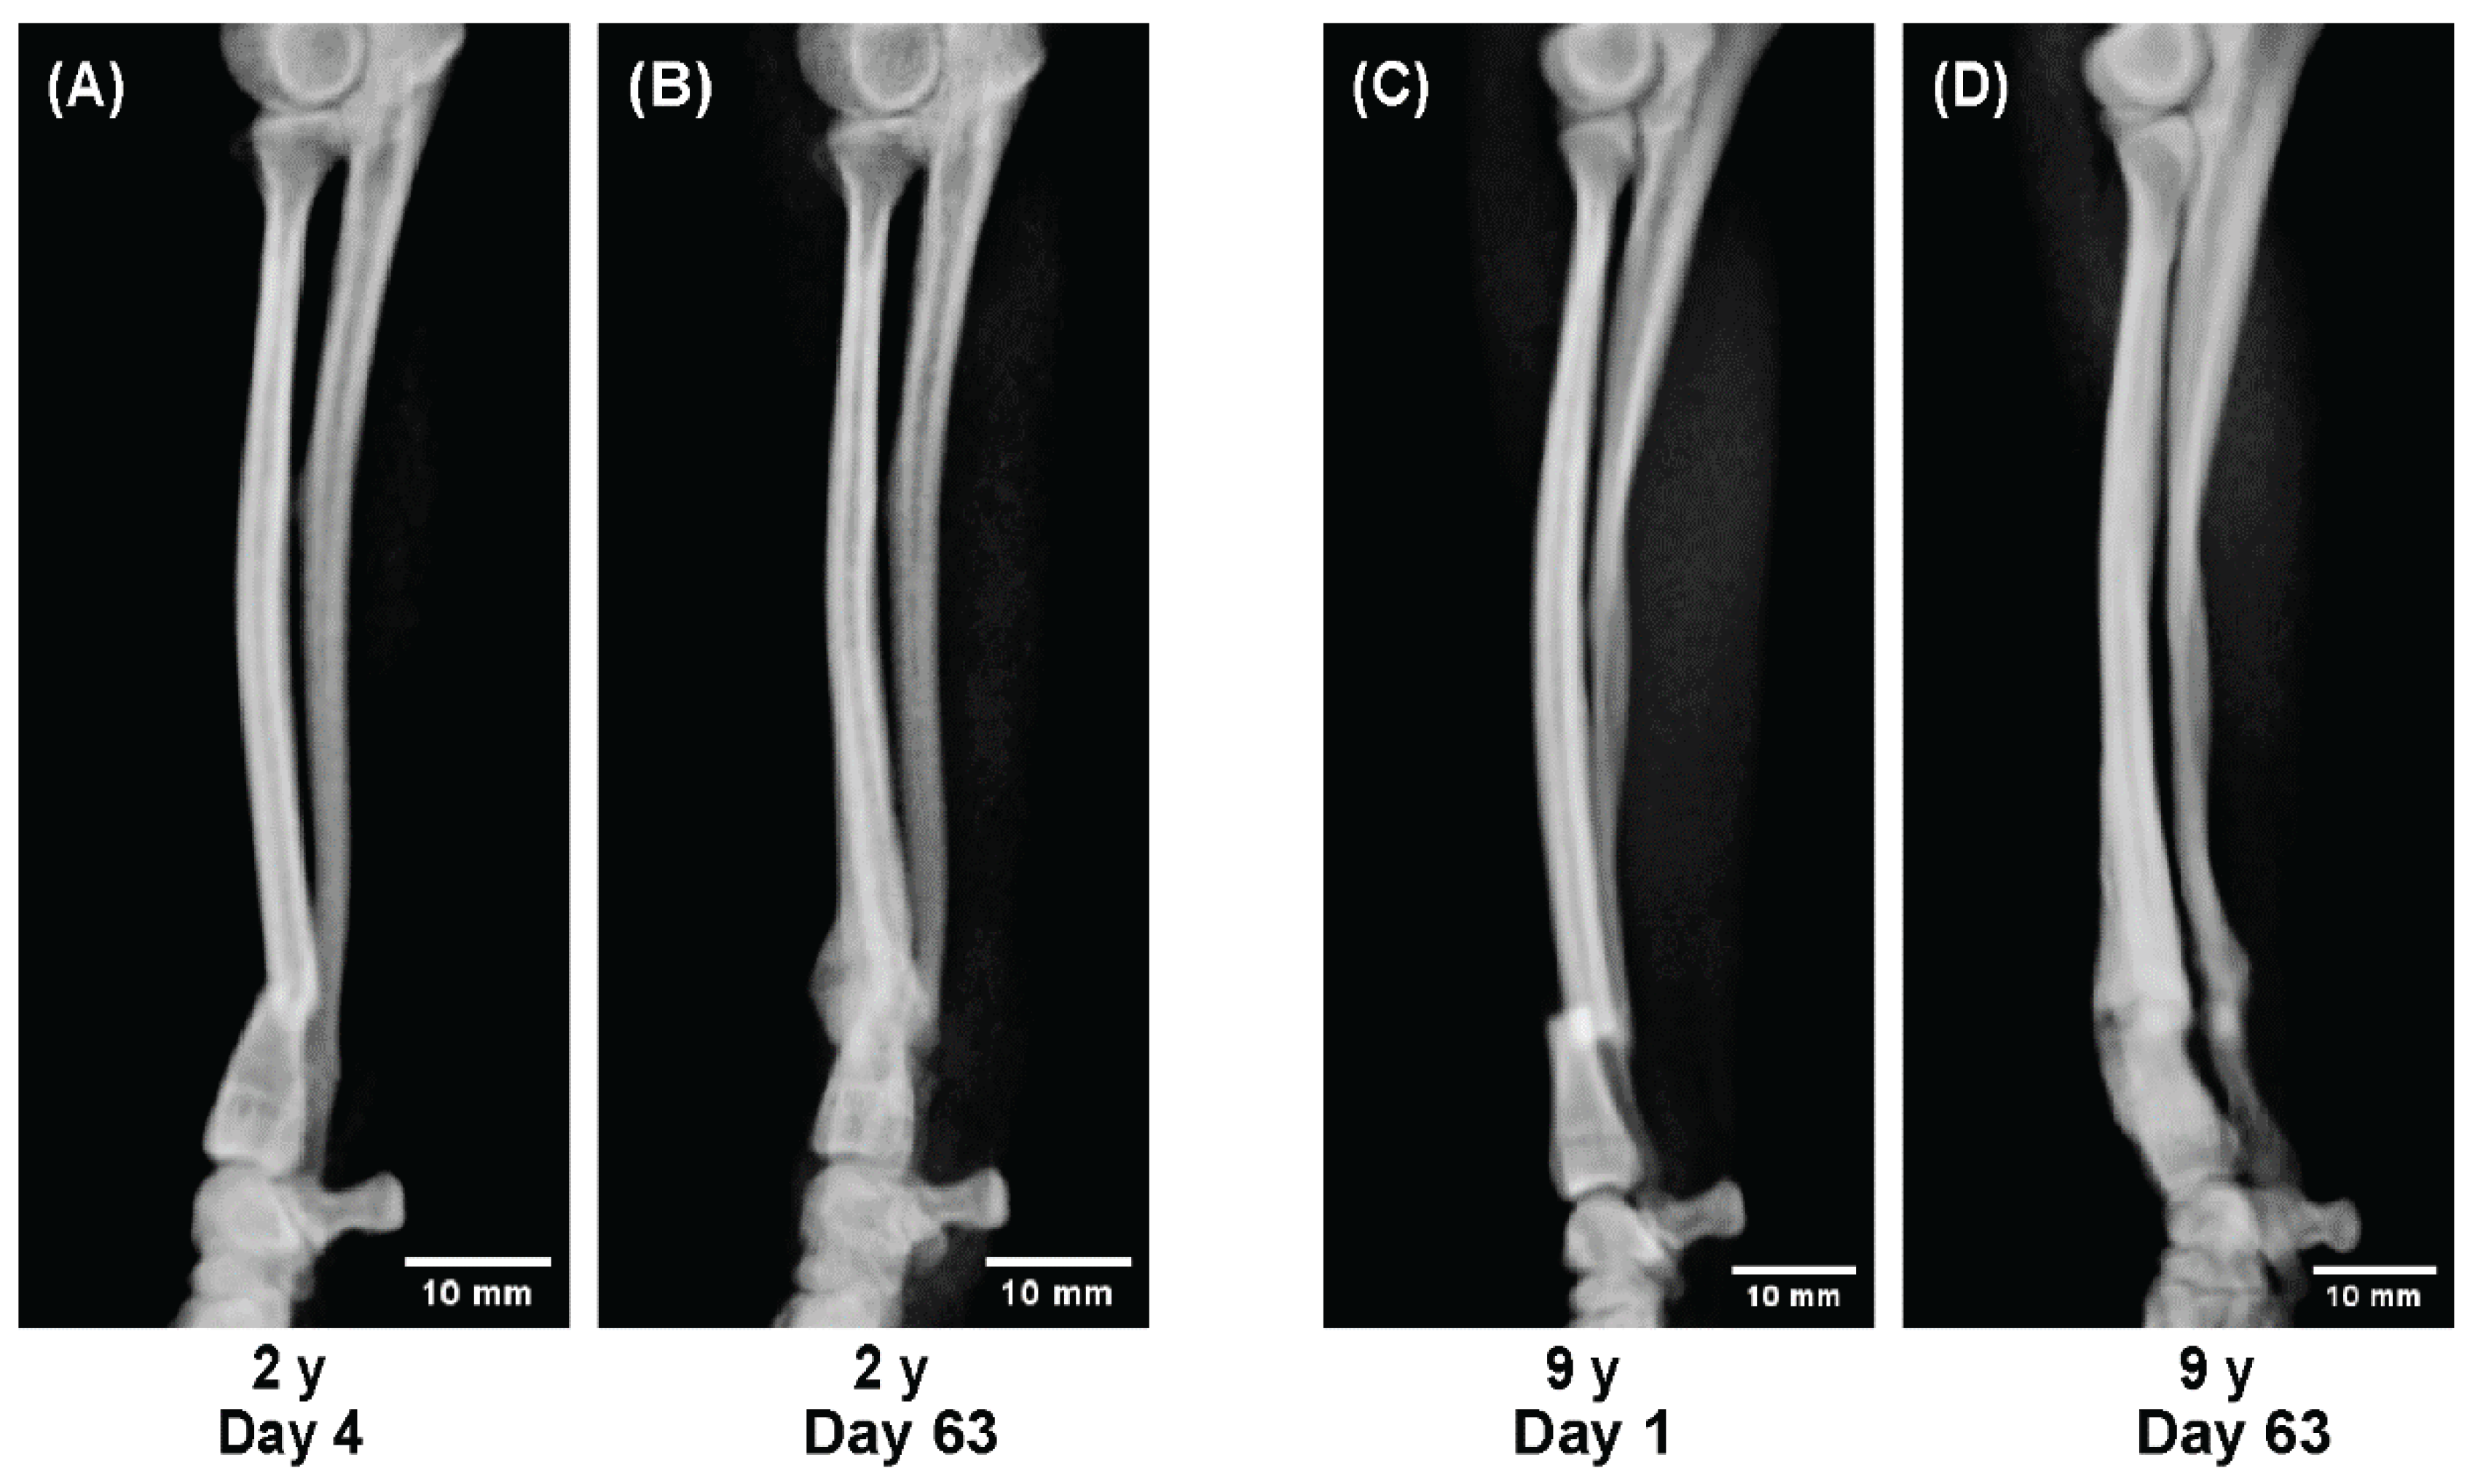

- A 5-month-old dog showing rapid callus proliferation (juvenile stage),

- Dogs aged 11 and 19 months showing reduced callus formation (adolescent stage), and

- Dogs aged 2 and 9 years showing stable but slower consolidation (adult to senior stage).

- A sequential radiographic series of a 5-month-old dog,

- Comparative observations between 11 and 19 months, and

- Between 2 and 9 years.

3.5. Radiographic Comparison by Age